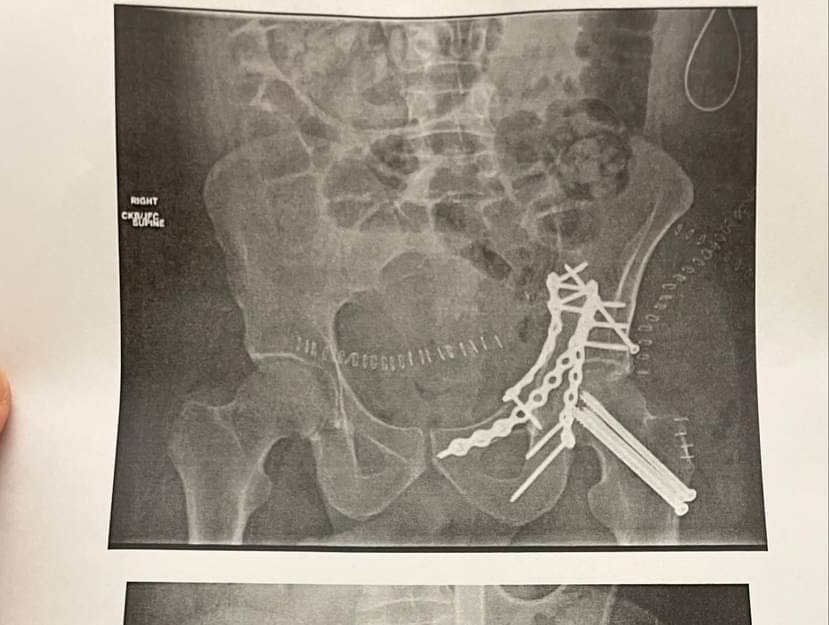

On July 30 , Caleb was seriously injured in a jet ski accident in San Diego, CA that left him with a shattered pelvis and unable to work for 6 months at minimum. After emergency care and 2 extensive surgeries, he’s now facing a long road of recovery, including rehab, follow-up care, traveling back to Oklahoma, and basic living expenses during his downtime.